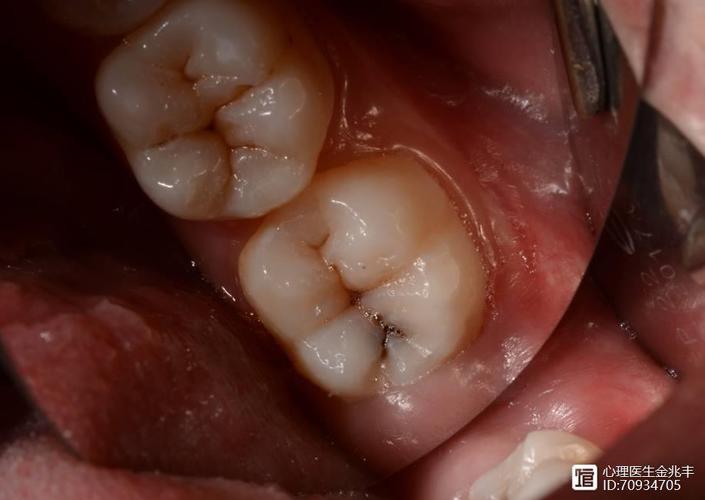

拔牙后的口腔护理同样重要

拔牙后,避免辛辣、坚硬食物,以免创口出血。同时,保持口腔卫生,轻柔刷牙,避免触碰伤口。某些中成药,如“健齿固龈,清血止痛”的制剂,可能帮助缓解牙龈炎症,但使用前需咨询医生。你是否曾因拔牙后牙龈出血而焦虑?选择合适的药物或食疗方法,如食用蜂蜜或温盐水漱口,或许能减轻不适。